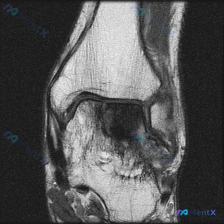

看到一份膝关节MRI的读片需求,核心问题是半月板异常,我整理了完整的分析思路,分享给大家。 病例影像基础信息 这是一张膝关节矢状位T2加权MRI,观察层面为膝关节外侧室,可显示股骨外侧髁、胫骨外侧平台、外侧半月板体部结构。 系统性影像学发现 1. 骨骼与关节软骨:股骨、胫骨骨皮质信号正常,骨髓无异常...